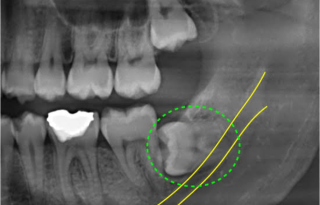

みなさんは親知らずって生えてますか?

みのりは右下の親知らずが

めっちゃキレイに真っ直ぐ生えて。

数年前にレントゲンを撮ったところ

なんと左下の親知らずが…

こんなことになってるのが判明しました…😇

どういうこと????!

横たわっている

ですって???!

しかもこの横たわり方、

「仕方なく」じゃなくて

完全にくつろいでる角度なんですよ。